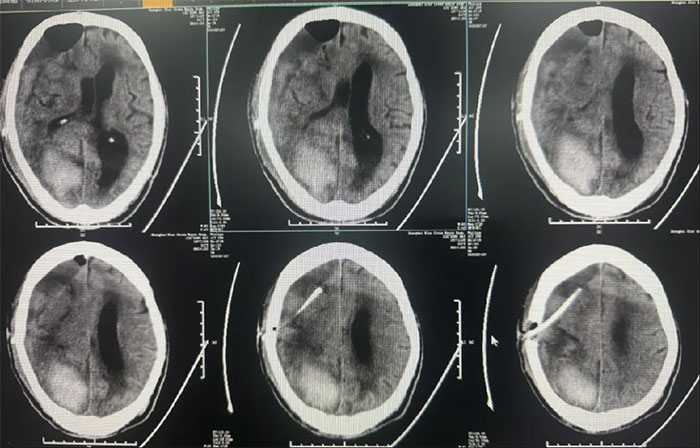

右顶枕叶出血,右侧额颞顶部亚急性硬膜下血肿,大脑镰下疝形成。

硬脑膜下钻孔引流术(长程引流管),引流管自右侧锁骨下皮肤穿出引流;

术后中线偏移明显改善,颅内压降低,停用脱水药物;

● 硬膜下血肿引流15天后拔管,中线基本复位,硬膜下血肿较前明显减少;